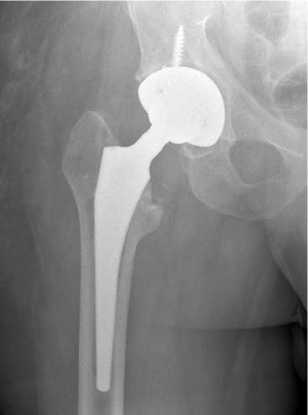

При повторной госпитализации через семь месяцев в НМИЦ ФПИ выполнена трехкратная пункция пери-имплантного пространства левого тазобедренного сустава. Роста микроорганизмов не выявлено. Перед вторым этапом эндопротезирования функциональные показатели сустава по шкале HHS — 64, по шкале WOMAC — 32, выраженность болевого синдрома по шкале ВАШ — 2 балла. 17.11.2023 произведен второй этап эндопротезирования в объеме удаления артикулирующего спейсера, тотального бесцементного эндопротезирования левого тазобедренного сустава Beijing Montagne Medical device / Zimmer (рис. 3).

Рис. 3. Рентгенограмма левого тазобедренного сустава пациента Ш. в первые сутки после операции тотального бесцементного эндопротезирования левого тазобедренного сустава Beijing Montagne Medical device / Zimmer